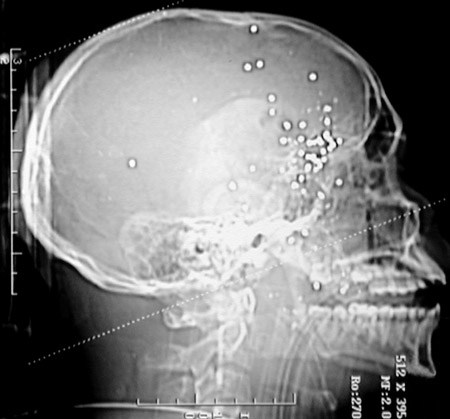

This head CT scan in sagittal view reveals numerous bright densities of similar size. This patient suffered a shotgun wound to the head at close range.